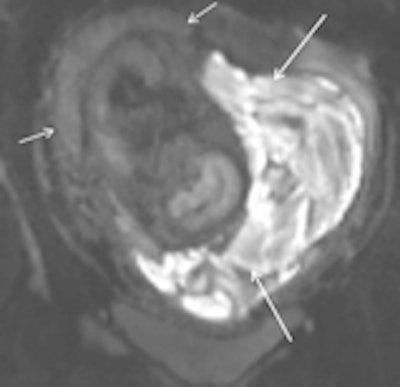

Subchorionic hemorrhage due to placenta abruption in a 30-year-old woman at 29 weeks gestation presented with acute pelvic pain and vaginal bleeding. Left: Coronal T1-weighted gradient-echo image (4.1/1.1, 10° flip angle) shows a large, hyperintense subchorionic hematoma (arrows). Middle and right: The intrauterine hematoma is mildly hyperintense to placenta on the sagittal T2-weighted half-Fourier RARE image (1000/90) (Middle) and markedly hyperintense to placenta on the sagittal diffusion-weighted image (b value, 800 sec/mm2) (right). Note the hematoma has hypo- and hyperintense areas, due to repeated bleeding. Short arrows indicate the placenta. All images courtesy of Dr. Gabriele Masselli.Masselli and colleagues on the ESUR Female Pelvic Imaging Subcommittee sought to develop guidelines for the appropriate imaging of acute abdominal and pelvic pain in established intrauterine pregnancy based on a detailed literature review and consensus expert opinion.